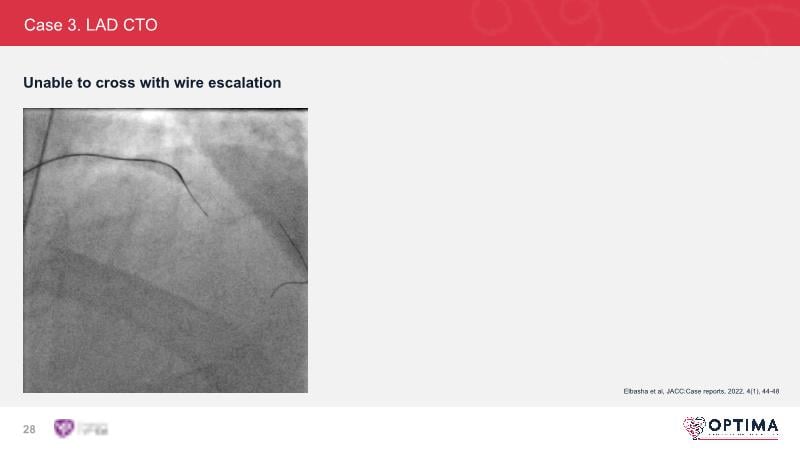

Cracking calcium: intravascular lithotripsy’s unique mode of action in treating calcified lesions – What's the evidence?

Watch this GulfPCR-GIM 2022 session to understand the unique mechanism of action of IVL, the use of intravascular imaging in calcium identification, the gender gap, disrupted CAD trials, and the evolution of treatment of calcified lesions together with the role of IVL.

- To understand the evolution of treating calcified lesions and the role of intravascular lithotripsy